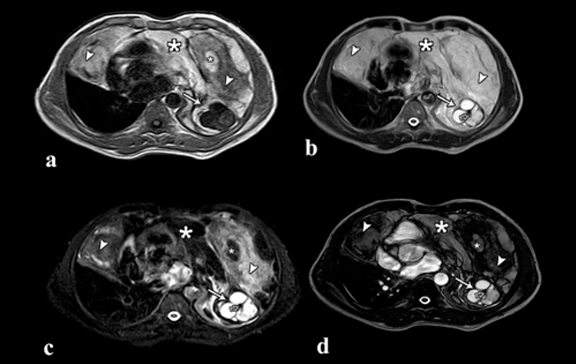

(a) Axial MRI T1W scan, (b) T2W scan, (c) Fat suppressed T2W and (d) BTFE images at the level of ventricles showing heterogeneous mass with solid component (arrow head), fat (*), cystic area (solid arrow) and nodular calcification (open arrow), occupying anterior half of right hemithorax and complete left hemithorax with pericardial invasion. (Page 623)